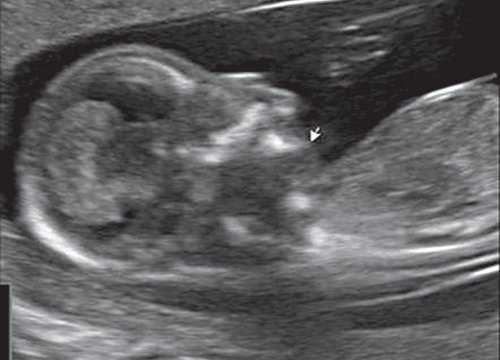

При эхографии в срок 13 недель 3 дня фетометрические параметры плода соответствовали гестационной норме, толщина воротникового пространства составила 1,5 мм; длина костей носа - по 2,5 мм. При трансвагинальном сканировании были обнаружены: затылочное энцефалоцеле размерами 7,4х3,5х3,7 мм (рис. 1), полидактилия кистей (рис. 2), увеличенные кистозно-измененные почки: правая - 28,5х21,3 мм; левая - 26,4х18,7 мм (рис. 3). Объем амниотической полости был нормальным для данного срока.

(Слева) Тот же плод. УЗИ брюшной полости, фронтальная плоскость. С обеих сторон определяются увеличенные кистозно-измененные почки. Необходимо помнить, что объем амниотической жидкости в I триместре может быть в норме, даже несмотря на тяжелое двустороннее поражение почек.

(Справа) Во время скринингового УЗИ плода в I триместре, выполненного во время последующей беременности у той же женщины, обнаружено энцефалоцеле. Синдром Меккеля-Грубера имеет аутосомно-рецессивный тип наследования, риск повторного возникновения составляет 25%.